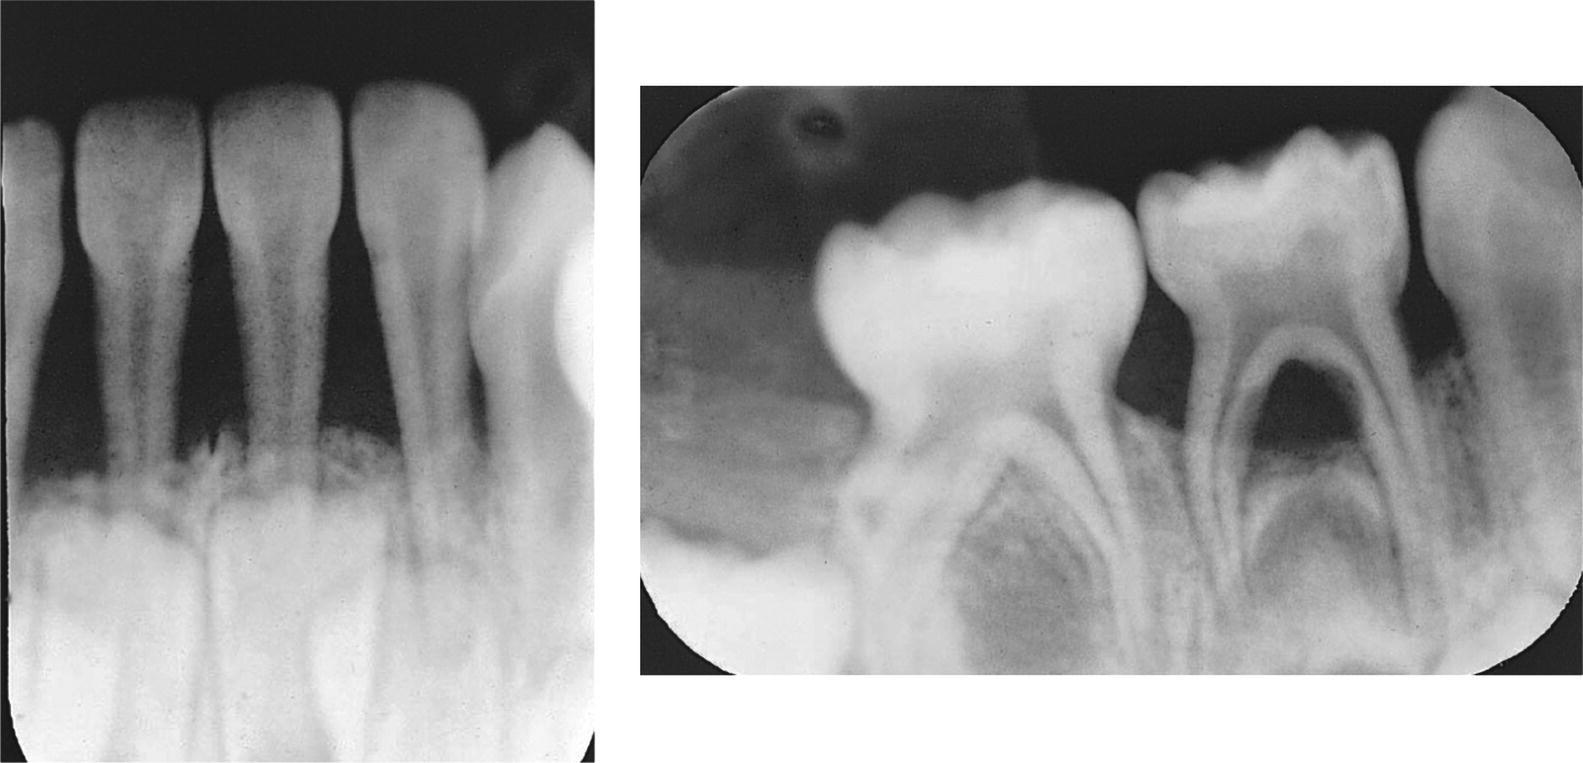

Dental X Ray Bone Loss . In addition, several other signs may alert your dentist to the possibility of osteoporosis: Reveal changes in the bone or in the root canal resulting from infection. This allows the surgeon to place. Reveal bone loss that accompanies gum disease. If you have significant bone loss, your dentist can use regenerative bone grafting to supplement the bone surrounding your teeth. The vertical bone defect is typically described by the tooth and surface where more bone loss is evident. Your dentist may assign a stage and a. Bone loss in the jaw and around teeth. If you note the bone between the mandibular second and third molar.